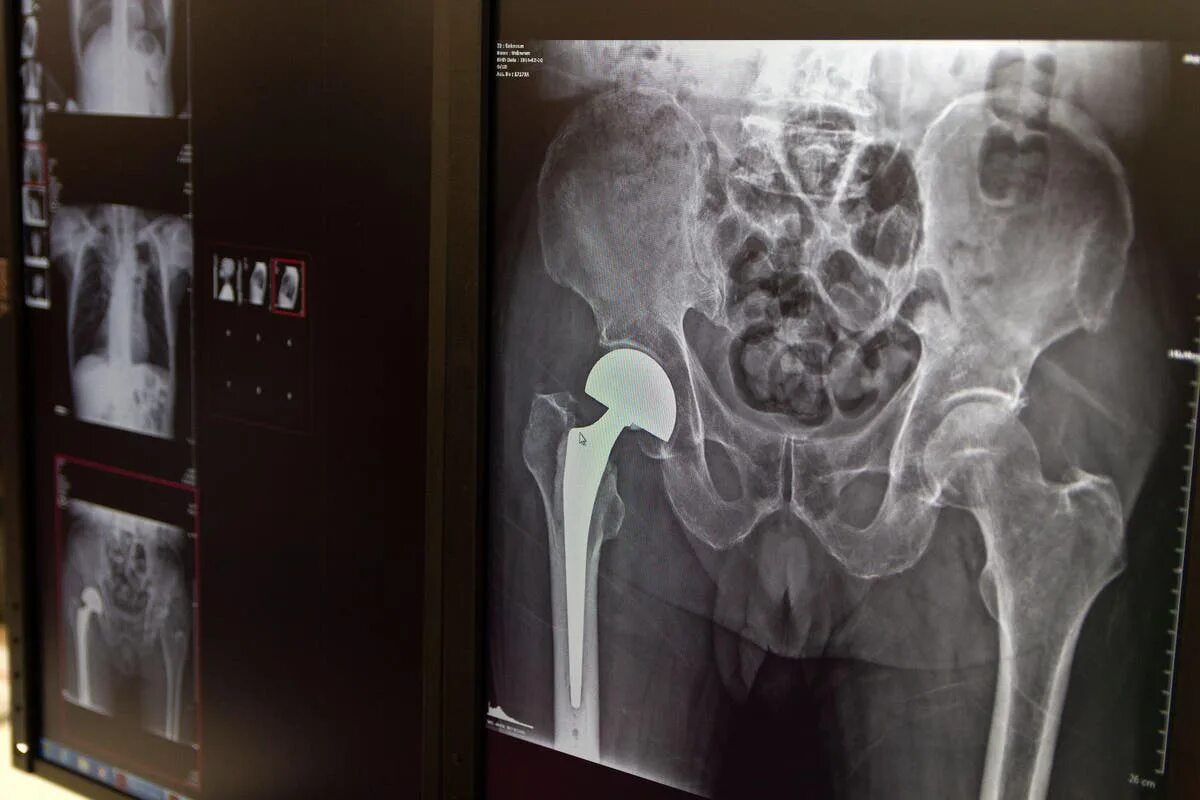

Мрт тазобедренного сустава в минске